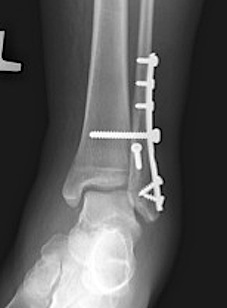

Many fractures can be treated without surgery, if the fractures are in place anatomically and can be maintained in this position with a cast. When there is significant displacement, or indications that there is significant ligament injury, surgery is recommended.

The main risk of the surgery is infection. This risk is low, about 1/100. Reducing swelling after surgery is critical, so keeping it up in the air when sitting or lying is very important. There can be some numbness around the incision, and there is a small risk of deep vein thrombosis. Usually there must be a period of non weight bearing for six weeks while the injury heals; however, early range of motion is useful to prevent or minimize stiffness. It can take 6 – 12 months to fully recover from these injuries.